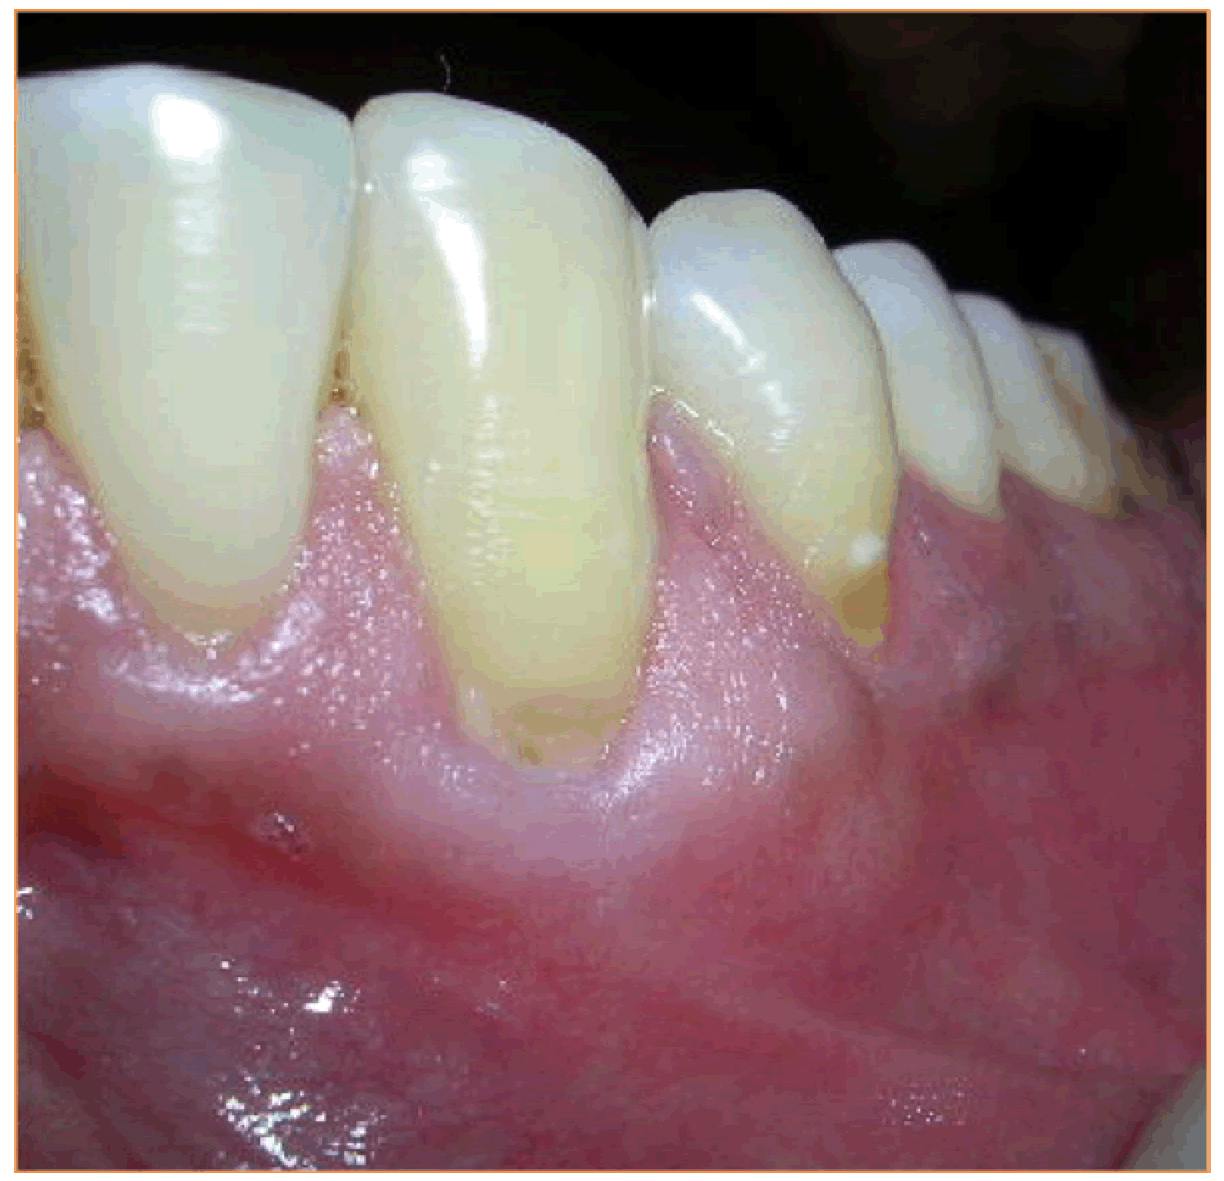

Case 2: A 31-year-old male presented with the chief complaint of sensitivity in the lower teeth and was clinically diagnosed as a case of Millers Class II recession in relation to 33 and 34 (Figure 5). The same surgical technique, as in Case 1, was used to place the connective tissue graft in the pouch created in relation to 33 and 34.

Figure 5: Millers Class II recession in relation to 33 and 34.